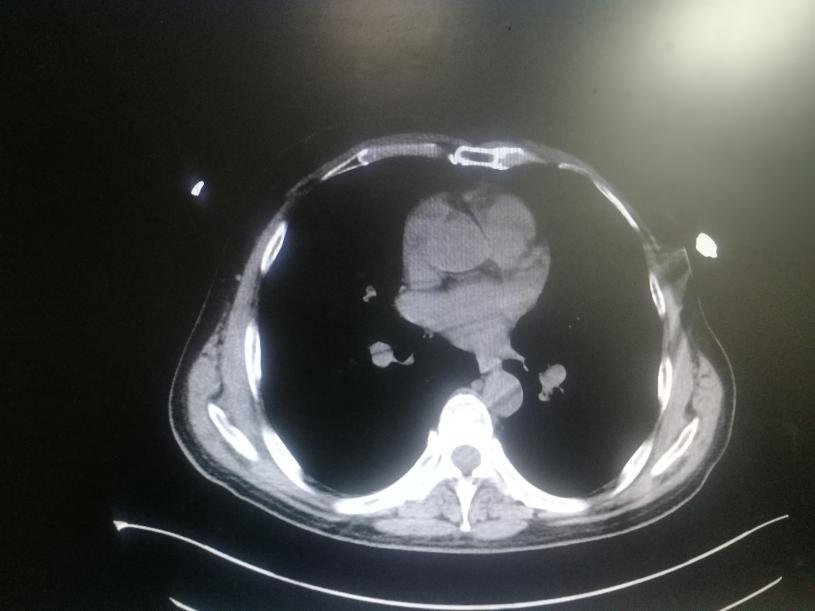

休息一晚后,疼痛没有像他想得那样缓解,反而越来越痛,于是在工友的搀扶下下来的医院就诊。在门诊我给他进行了简单的体格检查,发现患者胸骨压痛明显,无胸憋、气劲等不适,一般情况也还可以。同时行胸部正侧位片提示左侧第七肋骨骨折。

由于患者有摔伤史,同时胸部正侧位片提示第七肋骨骨折,因此我建议患者住院接受检查后进行治疗,患者面露难色,表示不想住院 ,后来在劝说下同意住院,以“肋骨骨折”收治。

入院后我给患者进行了比较全面的体格检查,患者四肢活动自如,左侧胸部压痛阳性,胸廓对称,左膝前肿胀,压痛阳性,前后抽屉实验阴性,内侧应力实验阴性,末端血运好。同时完善了血常规、肝功能、肾功能、凝血系列等常规检查,结果均未见明显异常 。

考虑到患者左侧第七肋骨骨折诊断明确,病情不严重,也不是开放性骨折,目前患者一般情况好,治疗上建议采取手术治疗,可以使用钛合金钢板来固定胸前肋骨,价位稍微贵一些,但是恢复快,患者表示拒绝进行手术治疗。故采取保守治疗,采用弹性胸带来固定肋骨,同时给予患者非甾体抗炎药物来减轻疼痛。